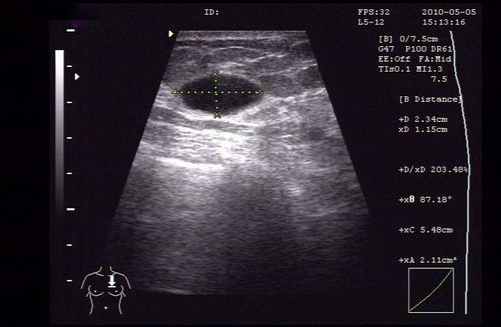

在超声报告里,对特别典型的“无回声”结节,有经验的超声医师会将其直接判断为“囊肿”,所谓囊肿,可以理解为一个薄薄的皮儿包着的一包水,这在乳腺囊性增生病里较为常见,可以单发,也可以多发。而多数的囊肿是良性的,无害的。

囊肿穿刺抽液是可以选择的诊断手段。如果穿刺囊液是血性的,提示有囊内乳头状瘤或者囊内癌的可能性,切除活检就是必要的。

△囊肿位置示意图